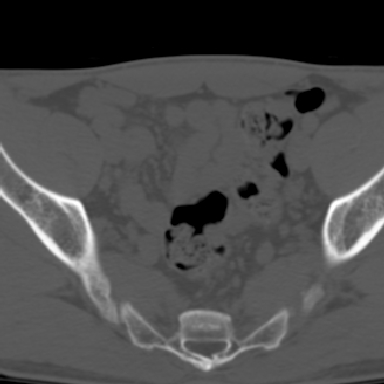

m 30 腰背部不适半年; 清晨时僵硬; 活动症状有所改善

双侧骶髂关节下2/3关节面模糊,毛糙,可见小囊状骨质破坏区.支持强直性脊柱炎.

强直性脊柱炎的早期改变!不仅表现为双侧骶髂关节,第5腰椎与骶椎间的关节突关节也有类似改变。

双侧骶髂关节下2/3关节面模糊,毛糙,髂骨侧可见小囊状骨质破坏区,骶髂关节间隙增宽(软骨破坏期)。支持早期强直性脊柱炎。

双侧骶髂关节下2/3关节面模糊、毛糙,可见小囊状骨质破坏区,呈虫咬状改变,周围可见增生硬化.支持强直性脊柱炎早期表现.

双侧骶髂关节髂骨面硬化,毛糙,小囊变,属于早期强直性脊柱炎